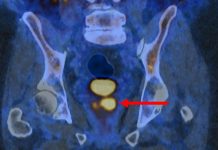

Studiul de Fază III a evaluat utilizarea scanării PSMA PET/CT, o tehnică ce implică injectarea unui radiofarmaceutic ce țintește antigenul specific de membrană prostatică (PSMA), care este supraexprimat în celulele canceroase de prostată.

„Scanarea PSMA PET/CT iluminează celulele canceroase de prostată într-un mod remarcabil, în special în cazul cancerelor mai agresive. Este rar să vedem o imagistică atât de puternică, care ar putea fi extrem de eficientă în clinică,” a declarat James Buteau, MD, medic specialist în medicină nucleară la Centrul de Cancer Peter MacCallum din Australia, care a prezentat cercetarea la EAU26. „Includerea acestei teste în îngrijirea clinică ar putea contribui la abordarea provocării majore a supradiagnosticării cancerului de prostată, care duce la tratamente inutile și, în cel mai rău caz, dăunătoare pentru cancerele care nu ar fi provocat niciodată vreun rău.”

Toți cei 660 de participanți recrutați în cadrul studiului desfășurat la nivelul Australiei au primit rezultate care indicau un risc scăzut sau intermediar de cancer de prostată, bazate pe scanarea MRI inițială, și prezentau factori de risc adiționali, precum creșterea scorului PSA sau un istoric familial de cancer. În mod normal, pacienții cu acest profil sunt trimiși la o biopsie de rutină pentru a confirma sau infirma prezența cancerului de prostată.

Participanții au fost randomizați fie pentru a suferi o biopsie standard, fie o scanare PSMA PET/CT. În grupul experimental, tehnica de imagistică a fost folosită pentru a identifica pacienții care nu aveau cancer sau care aveau unul cu risc scăzut sau creștere lentă, care probabil nu ar fi devenit niciodată periculos. Cei cu rezultate pozitive la scanare au primit ulterior o biopsie pentru a confirma suspiciunea de cancer de prostată.

Rezultatele au arătat că scanările PSMA PET/CT au redus procentul pacienților fără cancer de prostată care au primit o biopsie de la 44% la 22%, reducând la jumătate necesitatea acestei proceduri invazive. Aceasta susține utilizarea scanărilor PSMA PET/CT în practica de rutină pentru îmbunătățirea diagnosticării cancerului de prostată și reducerea numărului de biopsii inutile, fără a compromite detectarea cazurilor pozitive.

Deși costul și disponibilitatea limitează încă utilizarea pe scară largă a acestei tehnici de imagistică, scanările PSMA PET/CT devin tot mai accesibile pentru clinici din întreaga lume.

„A fi informat că există un risc de cancer de prostată provoacă o mare anxietate și îngrijorare,” a spus Louise Emmett, MD, PhD, director de teranostică și medicină nucleară la Spitalul St Vincent din Sydney. „Rezultatele noastre arată că PSMA PET/CT după MRI oferă o abordare ‘două în unul’ care poate determina cine are un cancer clinic semnificativ și cine este la risc scăzut și nu necesită o biopsie sau alte teste suplimentare.”